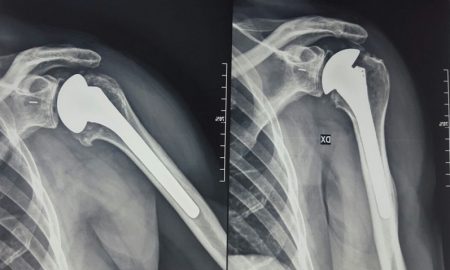

SIRACUSA – Tre focus dedicati alla chirurgia protesica articolare che continua a compiere importanti passi in avanti grazie all’utilizzo di metodi e...